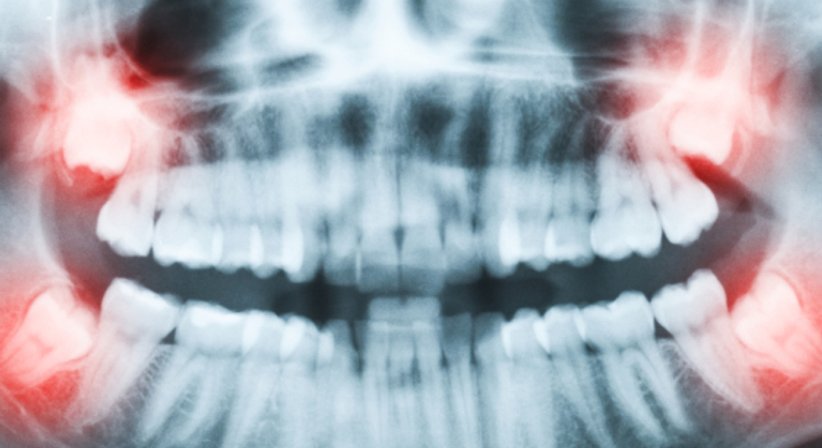

Von der Mitte aus gezählt sind Weisheitszähne die jeweils achten Zähne im oberen und unteren Kiefer. Bieten die Kiefer ein ausreichendes Platzangebot und brechen die Zähne in korrekter Position vollständig durch, dann sind Weisheitszähne nützliche Kauelemente. Ein nicht (vollständig) herausgewachsener Weisheitszahn kann hingegen die Kiefergesundheit und die Stellung anderer Zähne beeinträchtigen und verschiedene Komplikationen verursachen.

Weisheitszähne verursachen Komplikationen, wenn sie teilweise oder vollständig im Kieferknochen bleiben und die Kauebene nicht erreichen. Abhängig davon, ob der Zahn die Schleimhaut durchbricht oder nicht handelt es sich um einen teilretinierten, retinierten oder impaktierten Weisheitszahn.

Gründe für einen gestörten Durchbruch sind Platzmangel (der Kiefer ist nicht ausreichend groß um den Zahn aufzunehmen) oder falsche Verlagerung. Auch ein Weisheitszahn, der äußerlich nicht sichtbar ist kann Probleme bereiten, beispielsweise wenn er nicht waagrecht, sondern senkrecht wächst (verlagerter Weisheitszahn) und in weiterer Folge benachbarte Zähne schädigt oder zu einer Verschiebung der anderen Zähne führt. Bei teilretinierten Zähnen ist die Mundhygiene häufig erschwert, was zu kariösen Läsionen und Zahnfleischentzündungen führen kann. Bedingt durch retinierte Weisheitszähne kann es zur Bildung von Zysten kommen. Weitere mögliche Gründe für die Entfernung von Weisheitszähnen sind u.a. Verschiebungen innerhalb der Zahnbögen, Engstand von Zähnen und Schmerzen.